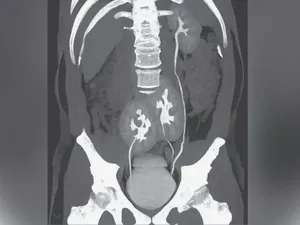

Pria Ini Idap Kondisi Langka Punya 3 Ginjal, Tak Sengaja Ketahuan saat ke Dokter

Pria India ini memiliki kondisi bawaan langka yang membuatnya memiliki tiga ginjal. Ketahuan secara tidak sengaja saat cek infeksi saluran kemih.